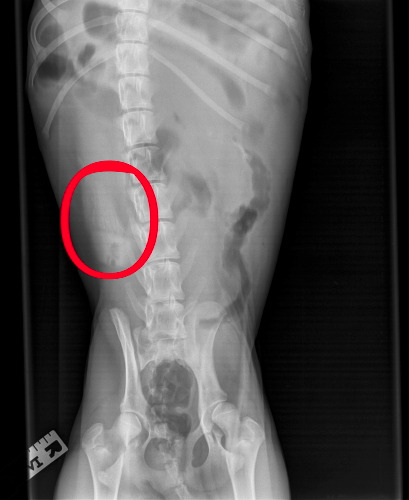

Am Dienstagmorgen ging es wieder an den Tropf, dieses Mal mit allem, was der Medizinschrank so hergibt: Von Elektrolyten über Magenschutz und Darmschleimhautaufbau bis zu Antibiotika. Alles rein! Nach einer halben Stunde floß ziemlich viel stinkendes Wasser aus dem Darm. Die Darmschleimhaut hatte sich endgültig verabschiedet. Zugleich aber zeigte Laani Interesse an Leckerchen und dann fraß sie einen ganzen Napf voll Hunde-"Astronautenkost" aus! Juhu! Am Abend ging es noch mal in die Praxis zum gleichen Spiel. Da Laani bis zum Abend wieder nichts gefressen hatte, wurde sie geröngt. Da sah man etwas, was den Verdacht auf einen Fremdkörper im wahrsten Sinne des Wortes erhärtete.

Der Ultraschall gab das gleiche Bild. Mittlerweile war die Praxis im Begriff, in den Feierabend zu gehen. Aber alle blieben, bzw. kamen, um ein Not-OP durchzuführen. Nachtschicht! Unsere Tierärzte sind unsagbar großartig! Da fehlen echt die Worte, um das zu beschreiben, was diese zusammen mit dem Helferteam geleistet haben. Nach Mitternacht waren wir wieder zu Hause, mit der schlafenden Laani und einem Infusionsgerät. Für Frauchen ging die Nachtschicht also weiter…

Was bei der OP zutage befördert wurde:

Der lang vermißte Kopf eines Silikon-Backpinsels! (Inzwischen gesäubert) Zustand des Objekts vor der Benutzung durch einen kleinen Riesenschnauzer:

Er mußte schon lange im Darm gelegen haben, und dann plötzlich doch an eine Stelle gewandert sein, wo es Probleme machte. Die Darmwand war in einem kritischen Zustand, so daß ein Stück Darm in einer Länge von einem Meter (!) entfernt wurde. Den Rest müssen die Selbstheilungskräfte der Natur reparieren, unterstützt von Astronautenkost und allem sonst, was Frauchen im Normalfall nie füttern würde.